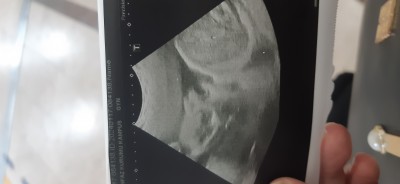

Bana çlğunlukla veriyor ya doktorum  devlet takipliyim ama ultrason cihazı cezaevinden gelmiş o yüzden hep cezainfaz kurumu yazıyor buda bebikim 27+6 dan

image

Cinsiyet erkek gibi duruyor

(664 puan)

Yok kızmış 13+6 da çikolata sayesinde öğrendik detaylıdaki özeldeki doktorda kız dedi ama fark etmez ister kız olsun ister erkek hayırlısı olsunda her hali kabulümüzdür